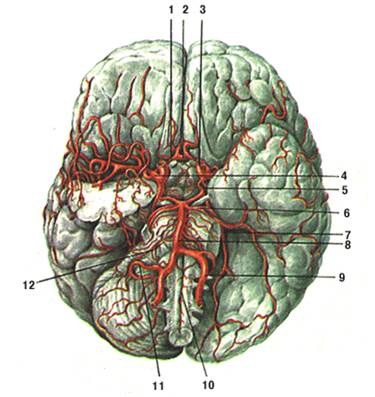

Анатомия: Задняя соединительная артерия мозга

Раздел: Фотоэссе